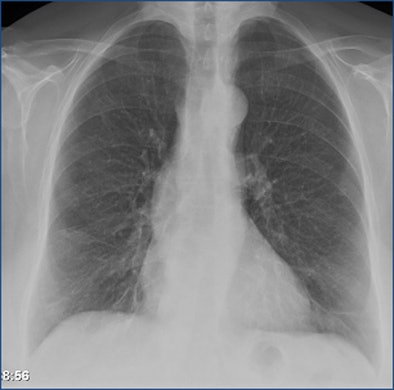

| Above is a false-negative chest x-ray. Below, an ultralow-dose 3-mm axial chest CT of the same patient acquired on a 320-detector-row scanner (Aquilion, Toshiba) and reconstructed with AIDR 3D shows a 7-mm nodule. At bottom, the coronal maximum-intensity projection shows a 7-mm nodule in the left lung and some atelectasis in the right lung. All images courtesy of Dr. Trond Aaløkken. |